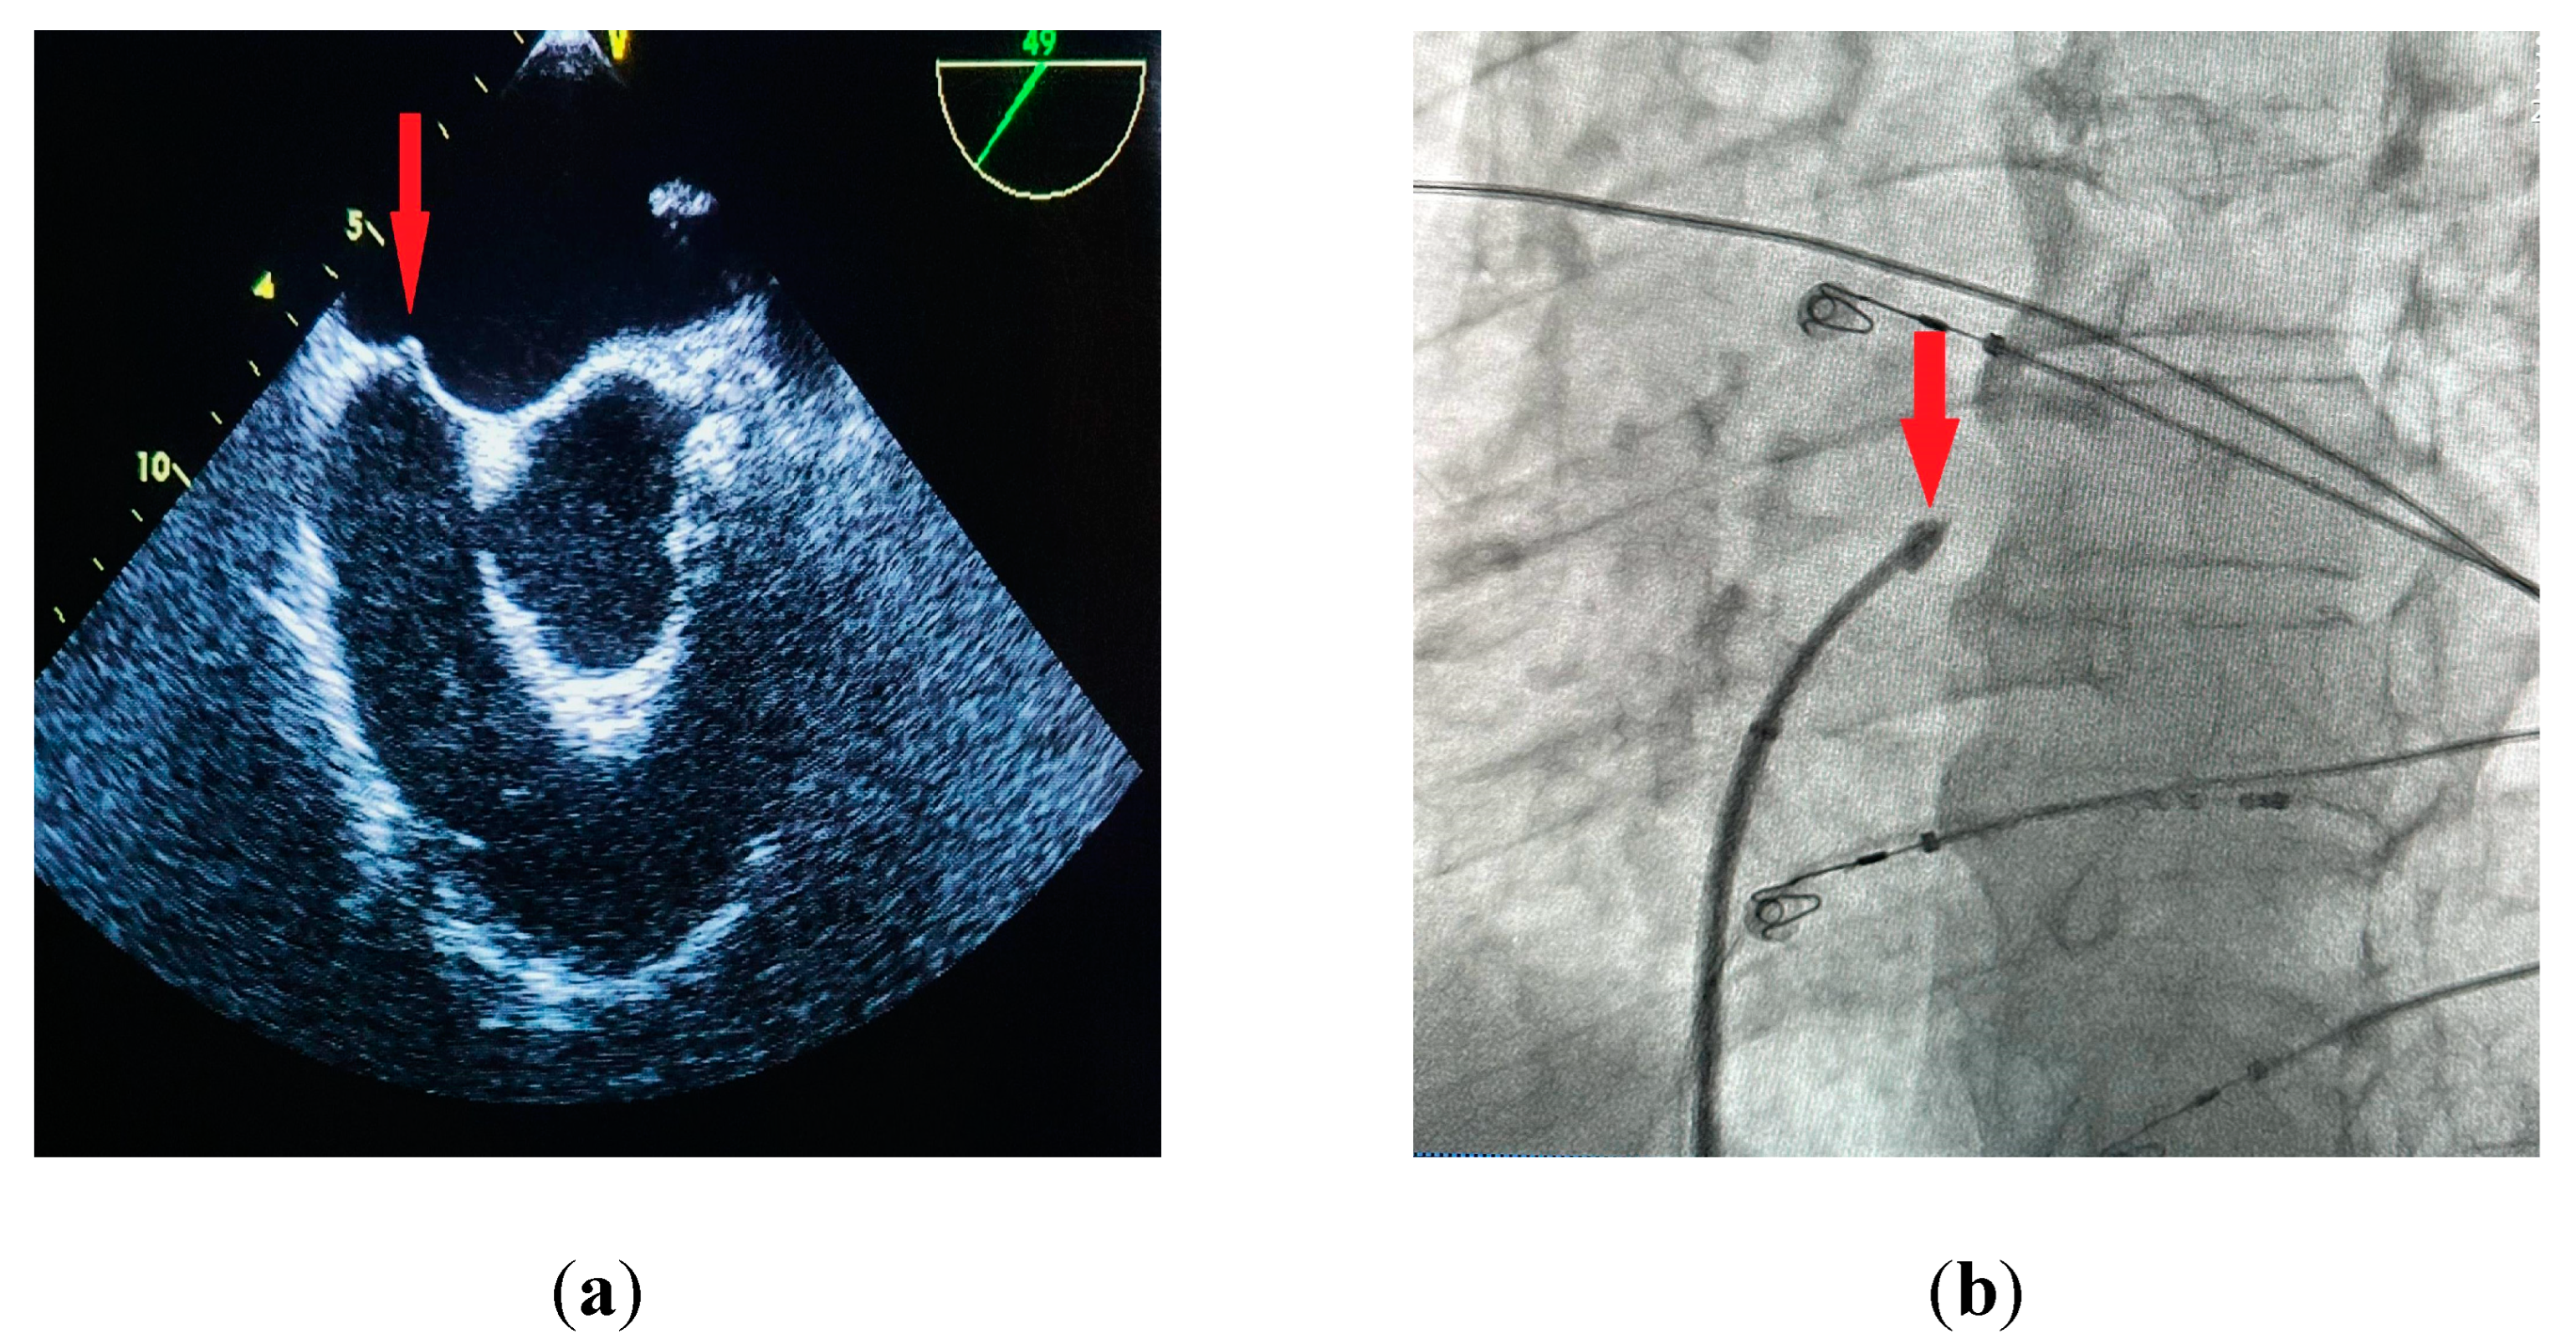

The standard technique for performing a TSP under fluoroscopic guidance involves obtaining venous access through the right femoral vein and placing a J-shaped guidewire into the superior vena cava. After advancing a transseptal sheath with a dilator over-the-wire into the superior vena cava, the guidewire is replaced with a transseptal needle with a stylet inside of it to avoid additional friction. After advancing the needle just below the tip of the dilator the stylet is removed and a syringe with contrast is connected to the needle. The System is then rotated to 4-5 o’clock (Figure 1a) and pulled down into the right atrium under the anteroposterior (AP) fluoroscopic view. Two “jumps” are encountered on the way down into the desired position on the interatrial septum - the first one after dropping from superior vena cava into the right atrium, and the second one after reaching the fossa ovalis. The assembly should then be carefully advanced into the final position (Figure 1b). A catheter placed in the coronary sinus is used as a landmark for the puncture; a pigtail catheter placed in the aortic root may also be used for additional orientation. Derejko et al. recently reported that a guidewire positioned between the superior and inferior vena cava can serve as another landmark guiding the TSP, as it should be running in direct vicinity to the FO in mid right anterior oblique (RAO) view [26]. Two independent fluoroscopic angles are used to confirm the correct position on the interatrial septum (IAS). In a 40° RAO view the assembly should be aligned so that the needle runs parallel to the coronary sinus catheter (Figure 1c). After verifying the correct position in the RAO view the needle is advanced outside the dilator under a 30° left anterior oblique (LAO) view (Figure 1d) and contrast is administered in order to confirm reaching the left atrium. Direct pressure monitoring from the transseptal needle may also be used [27]. IAS tenting can usually be observed before the needle passes into the left atrium (Figure 2a,b). The sheath with a dilator is carefully advanced over the needle into the left atrium. The needle is then withdrawn and replaced with a guidewire that is usually placed deep inside the left superior pulmonary vein. At this point the transseptal sheath can be safely exchanged for a dedicated transseptal system depending on the procedure type. Other modalities for TSP include the utilization of transesophageal (TEE) [27] or intracardiac echocardiography (ICE) [28] for direct visualization of the needle and its orientation relating to IAS and other heart structures.

Figure 2. (a) Interatrial septum (IAS) tenting visible on transesophageal echocardiography (red arrow), midesophageal 49° aortic valve short axis view; (b) IAS tenting visible on fluoroscopy before the puncture (red arrow), 30° left anterior oblique (LAO) view; (c) transseptal puncture - needle is advanced outside the dilator, 30° LAO view; (d) sheath with the dilator advanced into the left atrium. Visible contrast medium lining the IAS at the puncture site (red arrow), 30° LAO view.